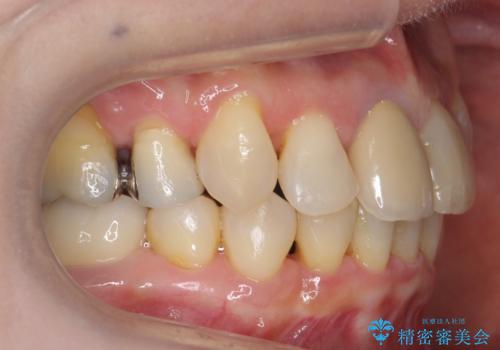

- ワイヤー矯正

- 八重歯の矯正を希望されて来院。

歯は入りきらないため、通常の抜歯矯正を行いました。

歯がご年齢的に動きにくいため、被せ物のやり替えを含めて治療期間の短縮を図りました。

矯正治療自体は2年半、虫歯治療等で1年ほどかかっています。

詰め物や被せ物のやり替えも併せて行っているため、治療期間を比較的短縮できました。